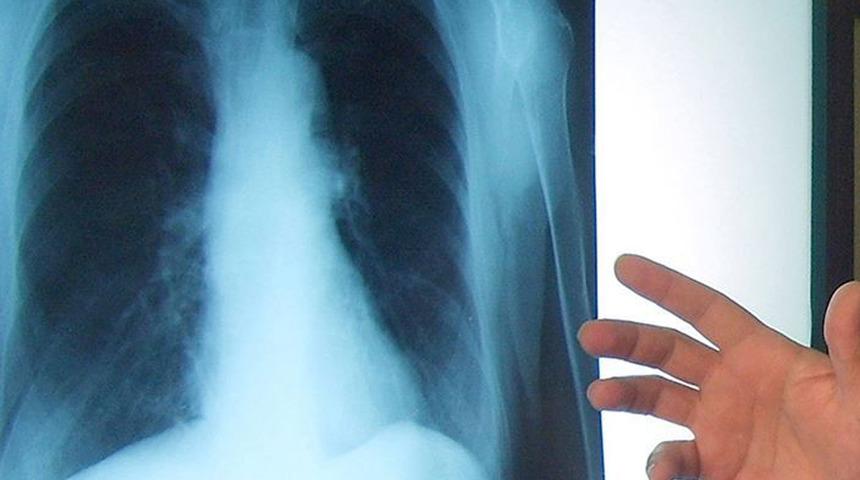

Her kanser türünde olduğu gibi akciğer kanserinde de erken tanının hayat kurtardığının unutulmaması gerektiğinin altını çizen Uzm. Dr. Huri Özkan Yılmaz, “Sigara içenlerin, ailesinde kanser öyküsü bulunanların, toksik maddelere maruz kalan meslek gruplarında çalışanların yıllık akciğer grafisi, 55 yaş üstü yüksek riskli gruplarda düşük doz tomografi ile taraması, nedeni açıklanamayan öksürük ve tekrarlayan zatürrelerde bronkoskopik inceleme mutlaka önerilmektedir. Bu pandemi sürecinde hastaların hastaneye gitmekten çekinmeleri tanılarda gecikmeye neden olmaktadır. Semptomu olan hastaların gecikmeden mutlaka göğüs hastalıkları polikliniğine başvurması önerilir” diyerek sözlerini noktaladı.